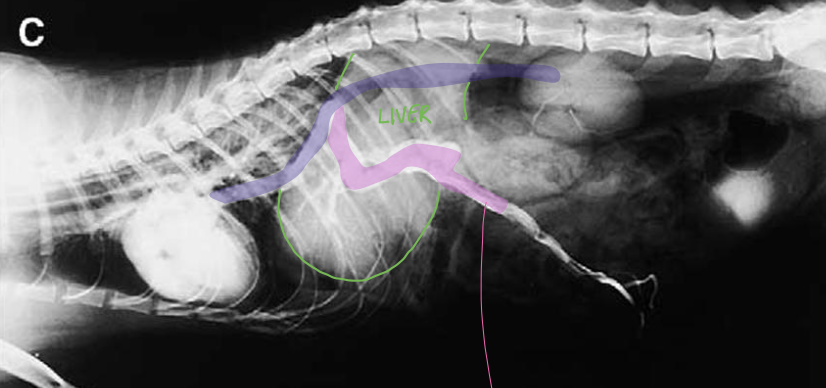

how does the liver appear grossly in animals affected by congenital portal systemic shunt?

liver is small with single anomalous vessels connecting portal circulation with systemic circulation

what does the image show?

congenital intrahepatic portosystemic shunts